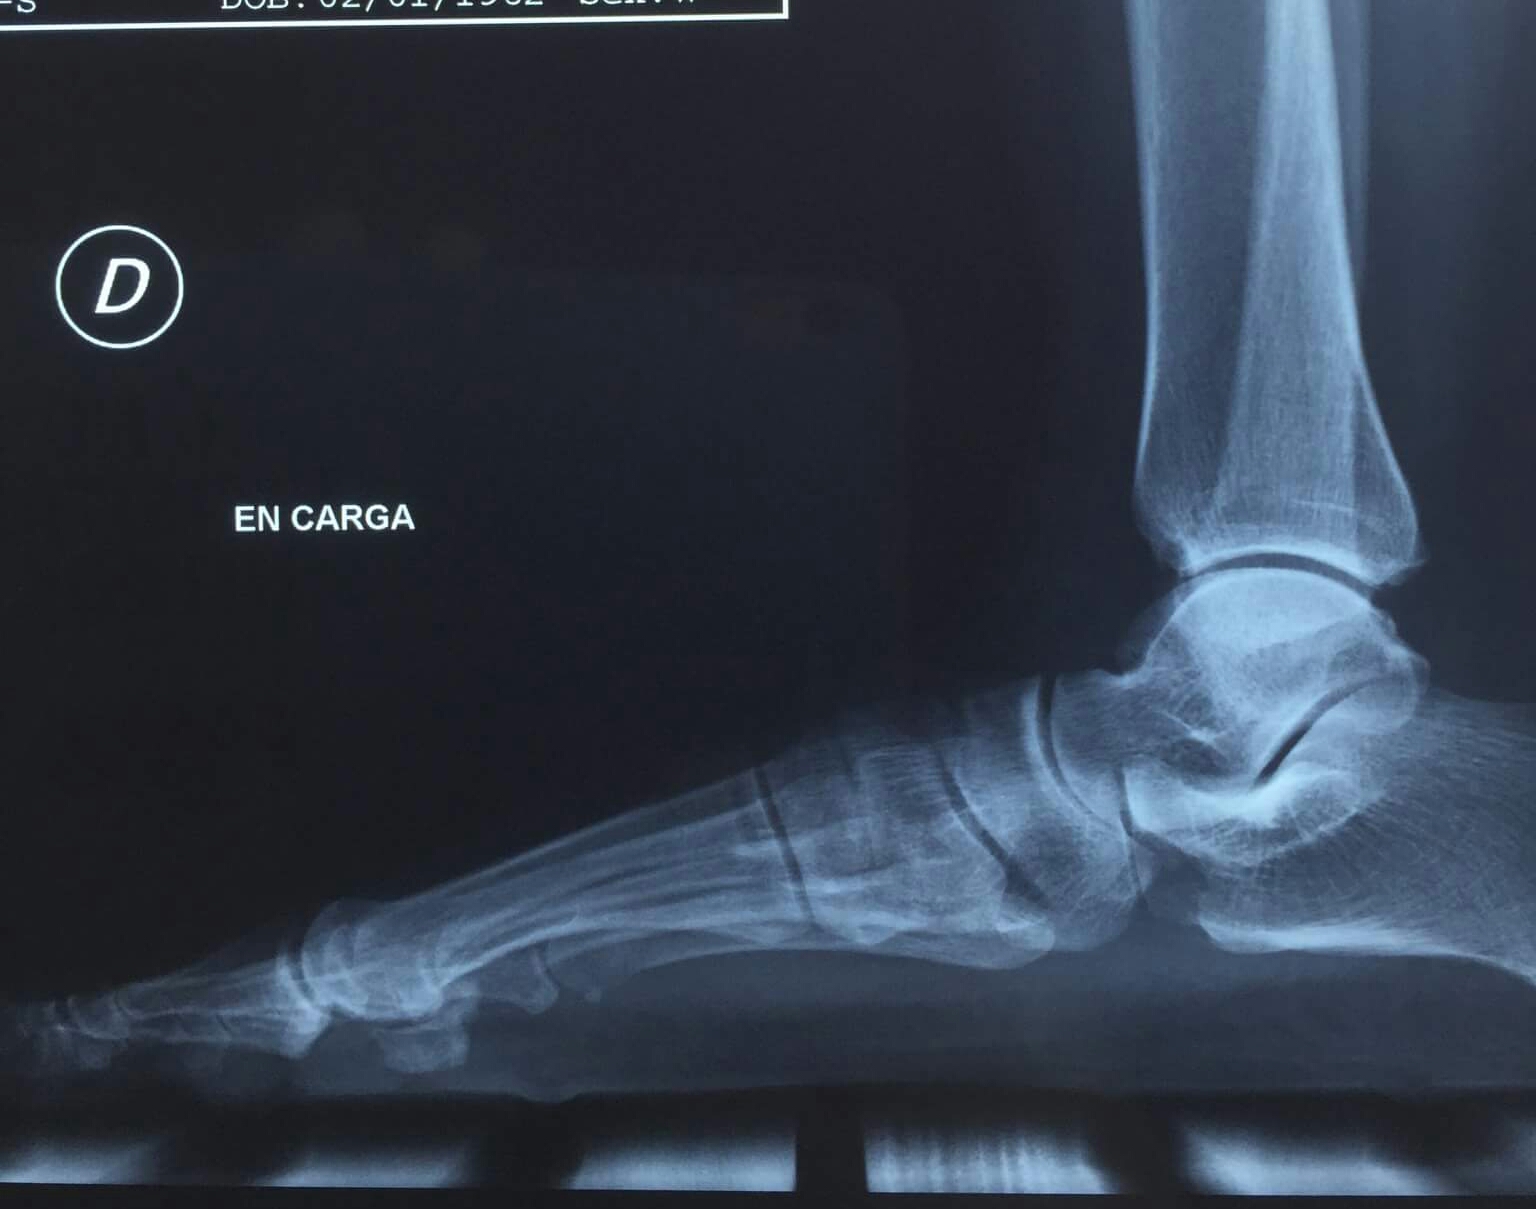

Podo Basas al Día Metatarsus primus elevatus. Uña incarnada (cirugía de onicocriptosis con fenol) What Is A Metatarsus Primus Elevatus The purpose of this study was to evaluate several radiographic parameters including first metatarsal elevation in patients with hallux rigidus compared to a matched control. In cases of significant metatarsus primus elevatus, a proximal osteotomy should be considered. Hallux rigidus and metatarsus primus elevatus (mpe) are associated, but their causal relationship remains unknown. Recent studies have supported a. A dorsiflexed. What Is A Metatarsus Primus Elevatus.

Podo Basas al Día Metatarsus primus elevatus. Uña incarnada (cirugía de onicocriptosis con fenol) What Is A Metatarsus Primus Elevatus Recent studies have supported a. Metatarsus primus elevatus is a clinical diagnosis in which the first metatarsal is dorsally deviated. Hallux rigidus and metatarsus primus elevatus (mpe) are associated, but their causal relationship remains unknown. Elevated first metatarsal, metatarsus primus elevatus (mpe), has been a topic of controversy. What is metatarsus primus elevatus? A dorsiflexed 1st ray (metatarsal) also known. What Is A Metatarsus Primus Elevatus.

The influence of hallux valgus and flatfoot deformity on metatarsus primus elevatus A What Is A Metatarsus Primus Elevatus What is metatarsus primus elevatus? The purpose of this study was to evaluate several radiographic parameters including first metatarsal elevation in patients with hallux rigidus compared to a matched control. Recent studies have supported a. Learn more about this condition. Metatarsus primus elevatus is a clinical diagnosis in which the first metatarsal is dorsally deviated. In cases of significant metatarsus. What Is A Metatarsus Primus Elevatus.

The influence of hallux valgus and flatfoot deformity on metatarsus primus elevatus A What Is A Metatarsus Primus Elevatus Several surgical approaches for treating hallux rigidus are. Recent studies have supported a. Hallux rigidus and metatarsus primus elevatus (mpe) are associated, but their causal relationship remains unknown. Metatarsus primus elevatus is a clinical diagnosis in which the first metatarsal is dorsally deviated. A dorsiflexed 1st ray (metatarsal) also known as metatarsus primus describes a deformity in which the 1st. What Is A Metatarsus Primus Elevatus.

Metatarsus Primus Elevatus The Chelsea Clinic What Is A Metatarsus Primus Elevatus In cases of significant metatarsus primus elevatus, a proximal osteotomy should be considered. Elevated first metatarsal, metatarsus primus elevatus (mpe), has been a topic of controversy. Hallux rigidus and metatarsus primus elevatus (mpe) are associated, but their causal relationship remains unknown. A dorsiflexed 1st ray (metatarsal) also known as metatarsus primus describes a deformity in which the 1st ray /metatarsal. What Is A Metatarsus Primus Elevatus.